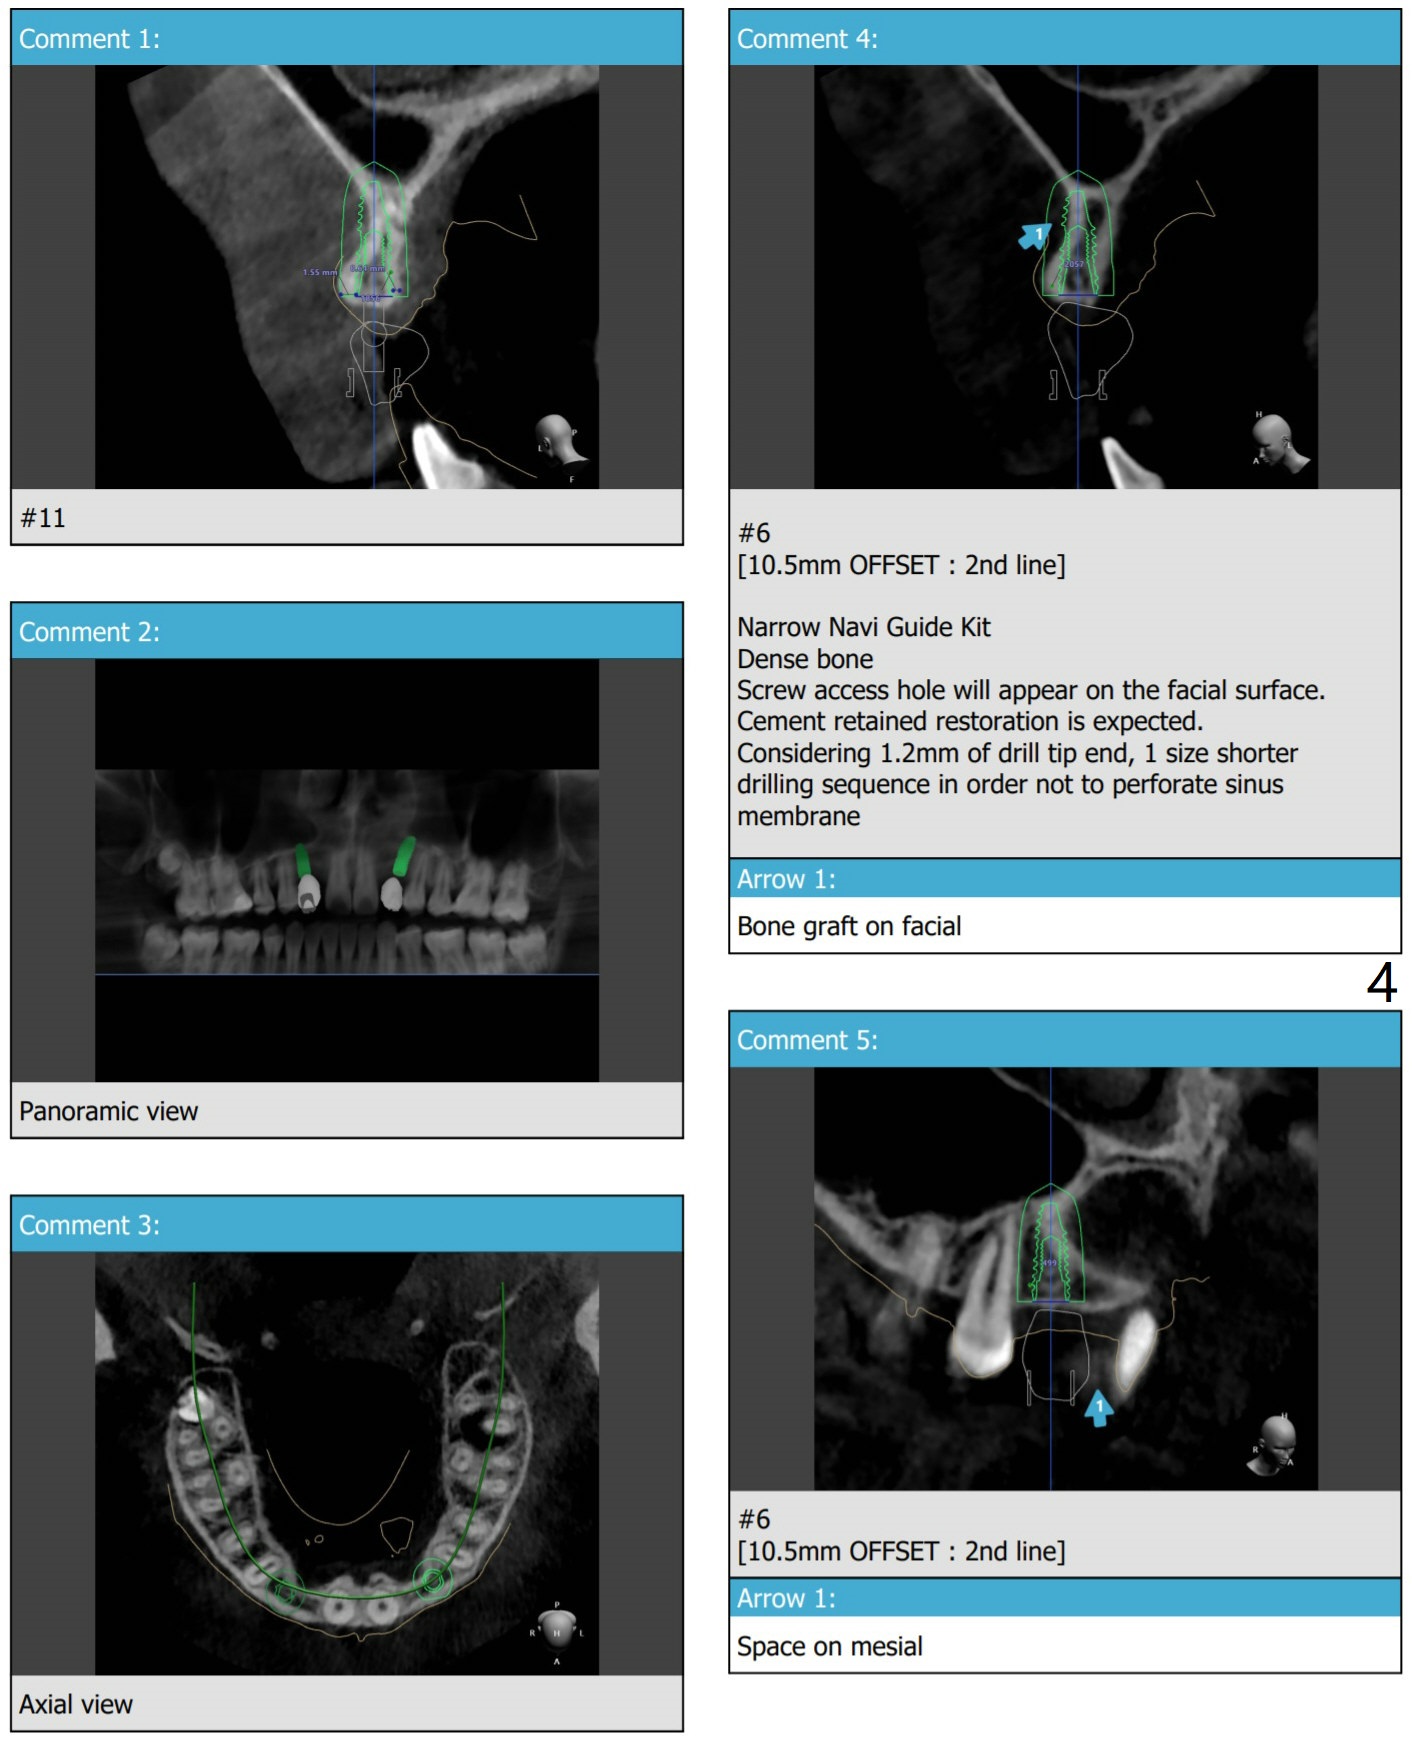

Return to No Deviation 尖牙即种 Oral Scanner